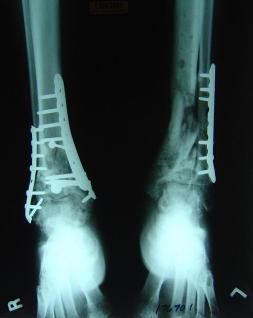

Pre-corrective surgery X-Rays of the damaged right & left legs / ankles

These x-rays were taken at Dr Armendariz’s office, just prior to performing any corrective surgery. As can be seen in these images,

there was no tibia bracing provided by Dr. Keller. Liam was released from Dr Keller’s care with instructions that full weight bearing could

be accomplished within 2 months of Keller’s last surgical procedure. The best example to examine is the second image (from the left) of the

top how. Notice how the bones that should be aligned with the tibia are in fact on the other side of the leg. The third image shows how badly

Liam’s left foot was twisted as a result of the pool placement of the external fixation. What is not obvious is that the screw at the bottom

of the plate on the right fibula missed being screwed into the plate.

Post-corrective surgery X-Rays of the damaged right & left legs / ankles

The first two x-rays show Liam’s left ankle and pelvis prior to the accident. For comparison purposes it is interesting to see the

differences. The next x-rays were taken after the corrective surgery performed by Dr. Armendariz. Noticed that Dr. Armendariz has used tibia

bracing and also aligned the bone fragments of the left leg so that they could heal in the proper orientation. The external fixation has been

removed and Liam’s left foot has been returned to a more natural alignment.